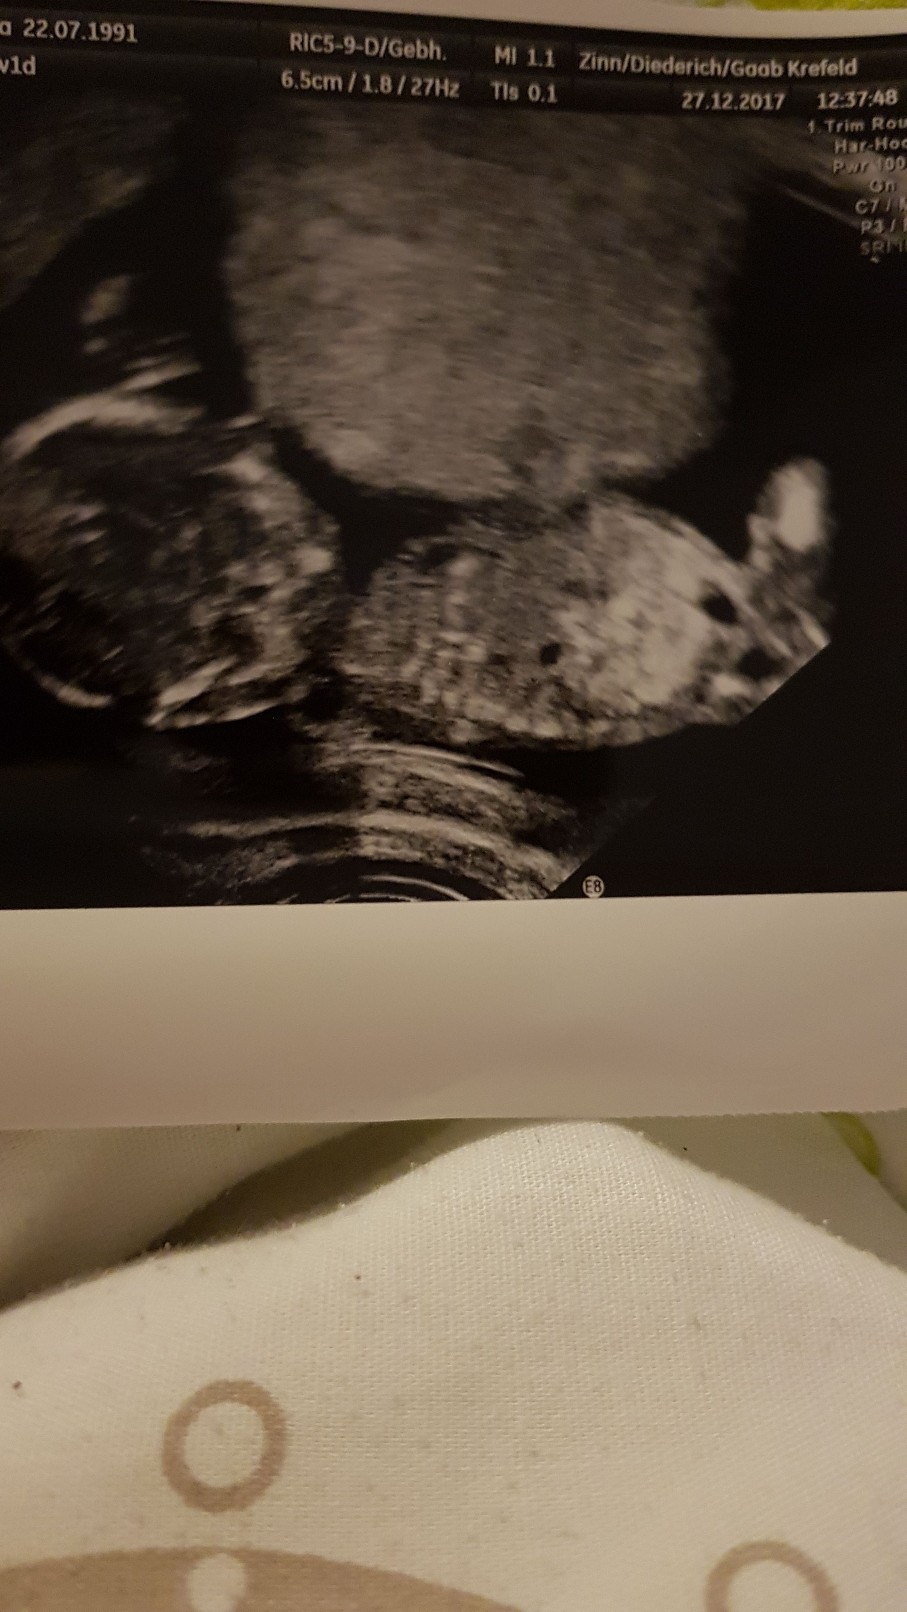

Sliczny duzy dzidzius[emoji5] Rosna nam dzieciaczki jak na drozdzach [emoji3]Zobacz załącznik 833446 a to zdjęcie z dzisiaj

Taaak teraz pewnie co USG to będą sporo większeSliczny duzy dzidzius[emoji5] Rosna nam dzieciaczki jak na drozdzach [emoji3]

5.5 cm, raczki, nozki, zoladek, nerki, pepowina unaczyniona. No i serduszko 160 u/' [emoji3] Ryzyko wad niskie.